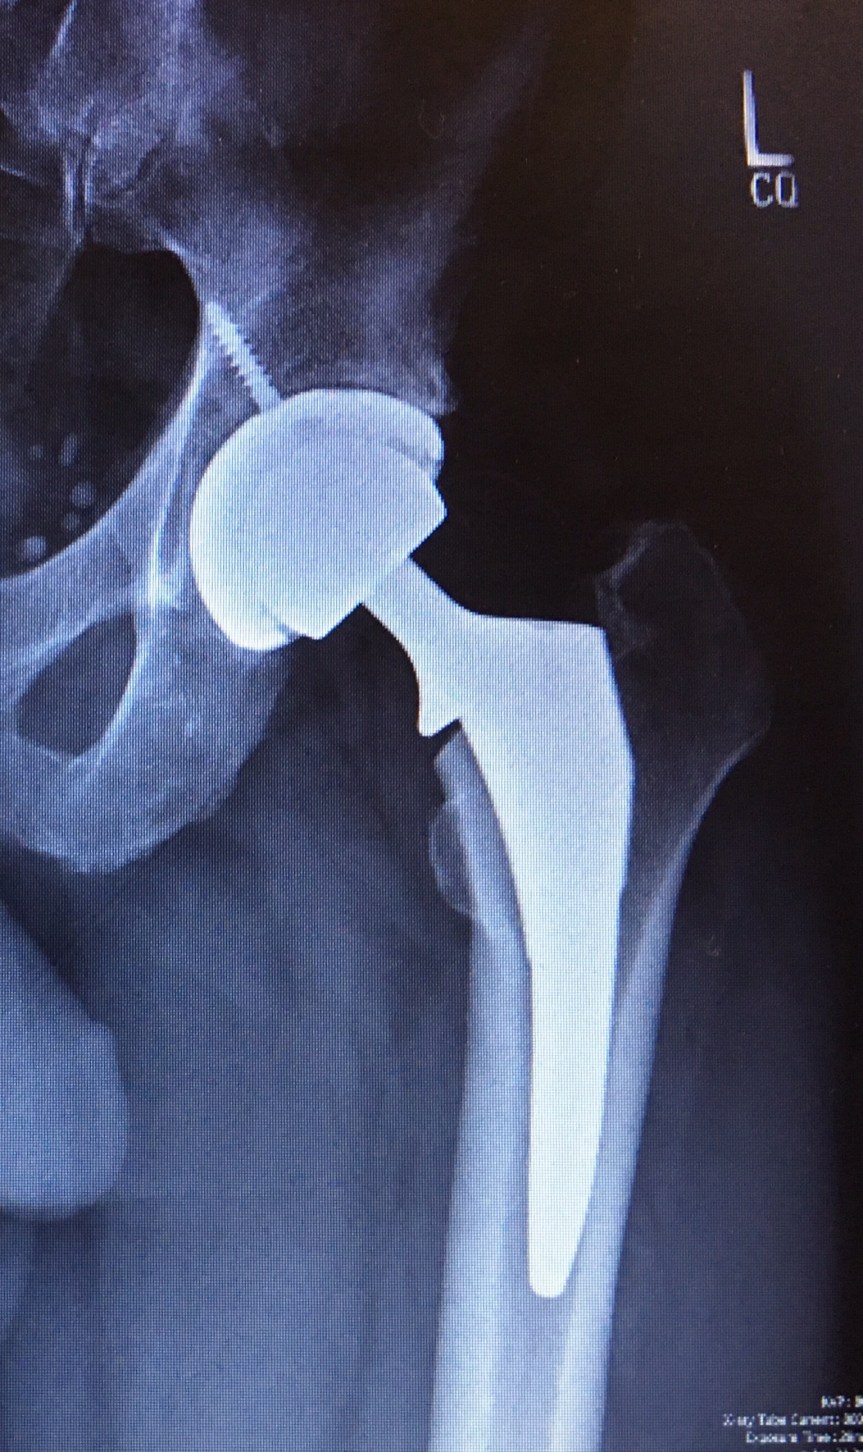

Today marks four weeks post hip replacement. I went in to see the surgeon so he could follow up and see how things are coming along. As usual, it is a long wait. Excellent surgeon, great doctor for talking to you straight, just wish he’d work on the time management side of the business. It’s at minimum an hour past your appointment time before you see him. That said, I’d not go anywhere else to get this operation done. Dr. Ball is the top of the line for orthopedic surgery. I’m doing really good. You wouldn’t have known that the first two weeks when I was totally depressed over being unable to do the simplest things. Of course, it didn’t help that the dog died and my wife is 3000 miles away. Anyway, I can almost put a shoe on and I’m now able to sleep on my side. I can walk without the cane and do 15 minutes on the exercise bike. I got fresh x-rays showing everything looking good and I am cleared to do whatever I can tolerate pain wise. I just can’t turn my leg outward for another month until everything is completely stable.